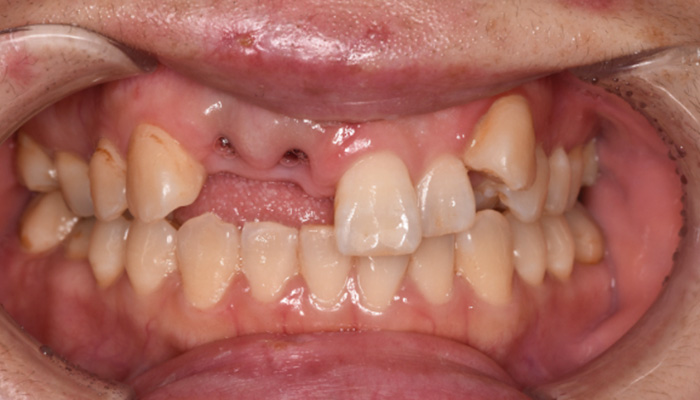

【50代女性】前歯のインプラント症例

「前歯は第一印象に関わるので失敗したくない」

治療中

治療後

前歯のインプラントで特に審美的に要求の高い患者様でしたので、当院で最も信頼性の高いインプラント治療プランをご選択いただきました。

| 主訴 | 抜けたままで放置していた前歯をインプラントにして綺麗にしたい。 |

| 治療期間 | 約4ヶ月 |

| 治療費 | 1本あたり550,000円(税別) |

| 治療内容 | 前歯のインプラント治療 |

| 治療のリスク | 前歯のインプラント治療では、審美性の問題や骨密度不足によるインプラントの不安定、神経損傷や感染のリスクがあり、術後の腫れや痛みも発生する可能性があります。 |